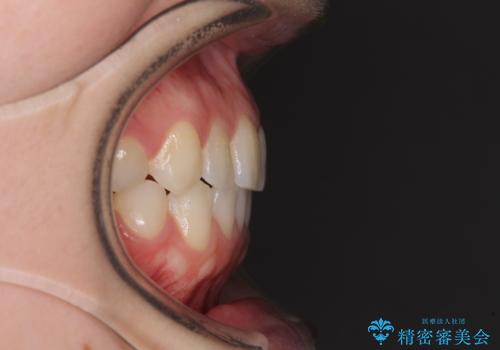

前歯のクロスバイトをインビザライン矯正で改善

- 前歯のデコボコと上下のクロスバイトを気にして来院された患者様です。

インビザラインを用い、IPR(歯と歯の間を削る)と歯列全体を拡大させることで、歯並びを整えていくこととしました。